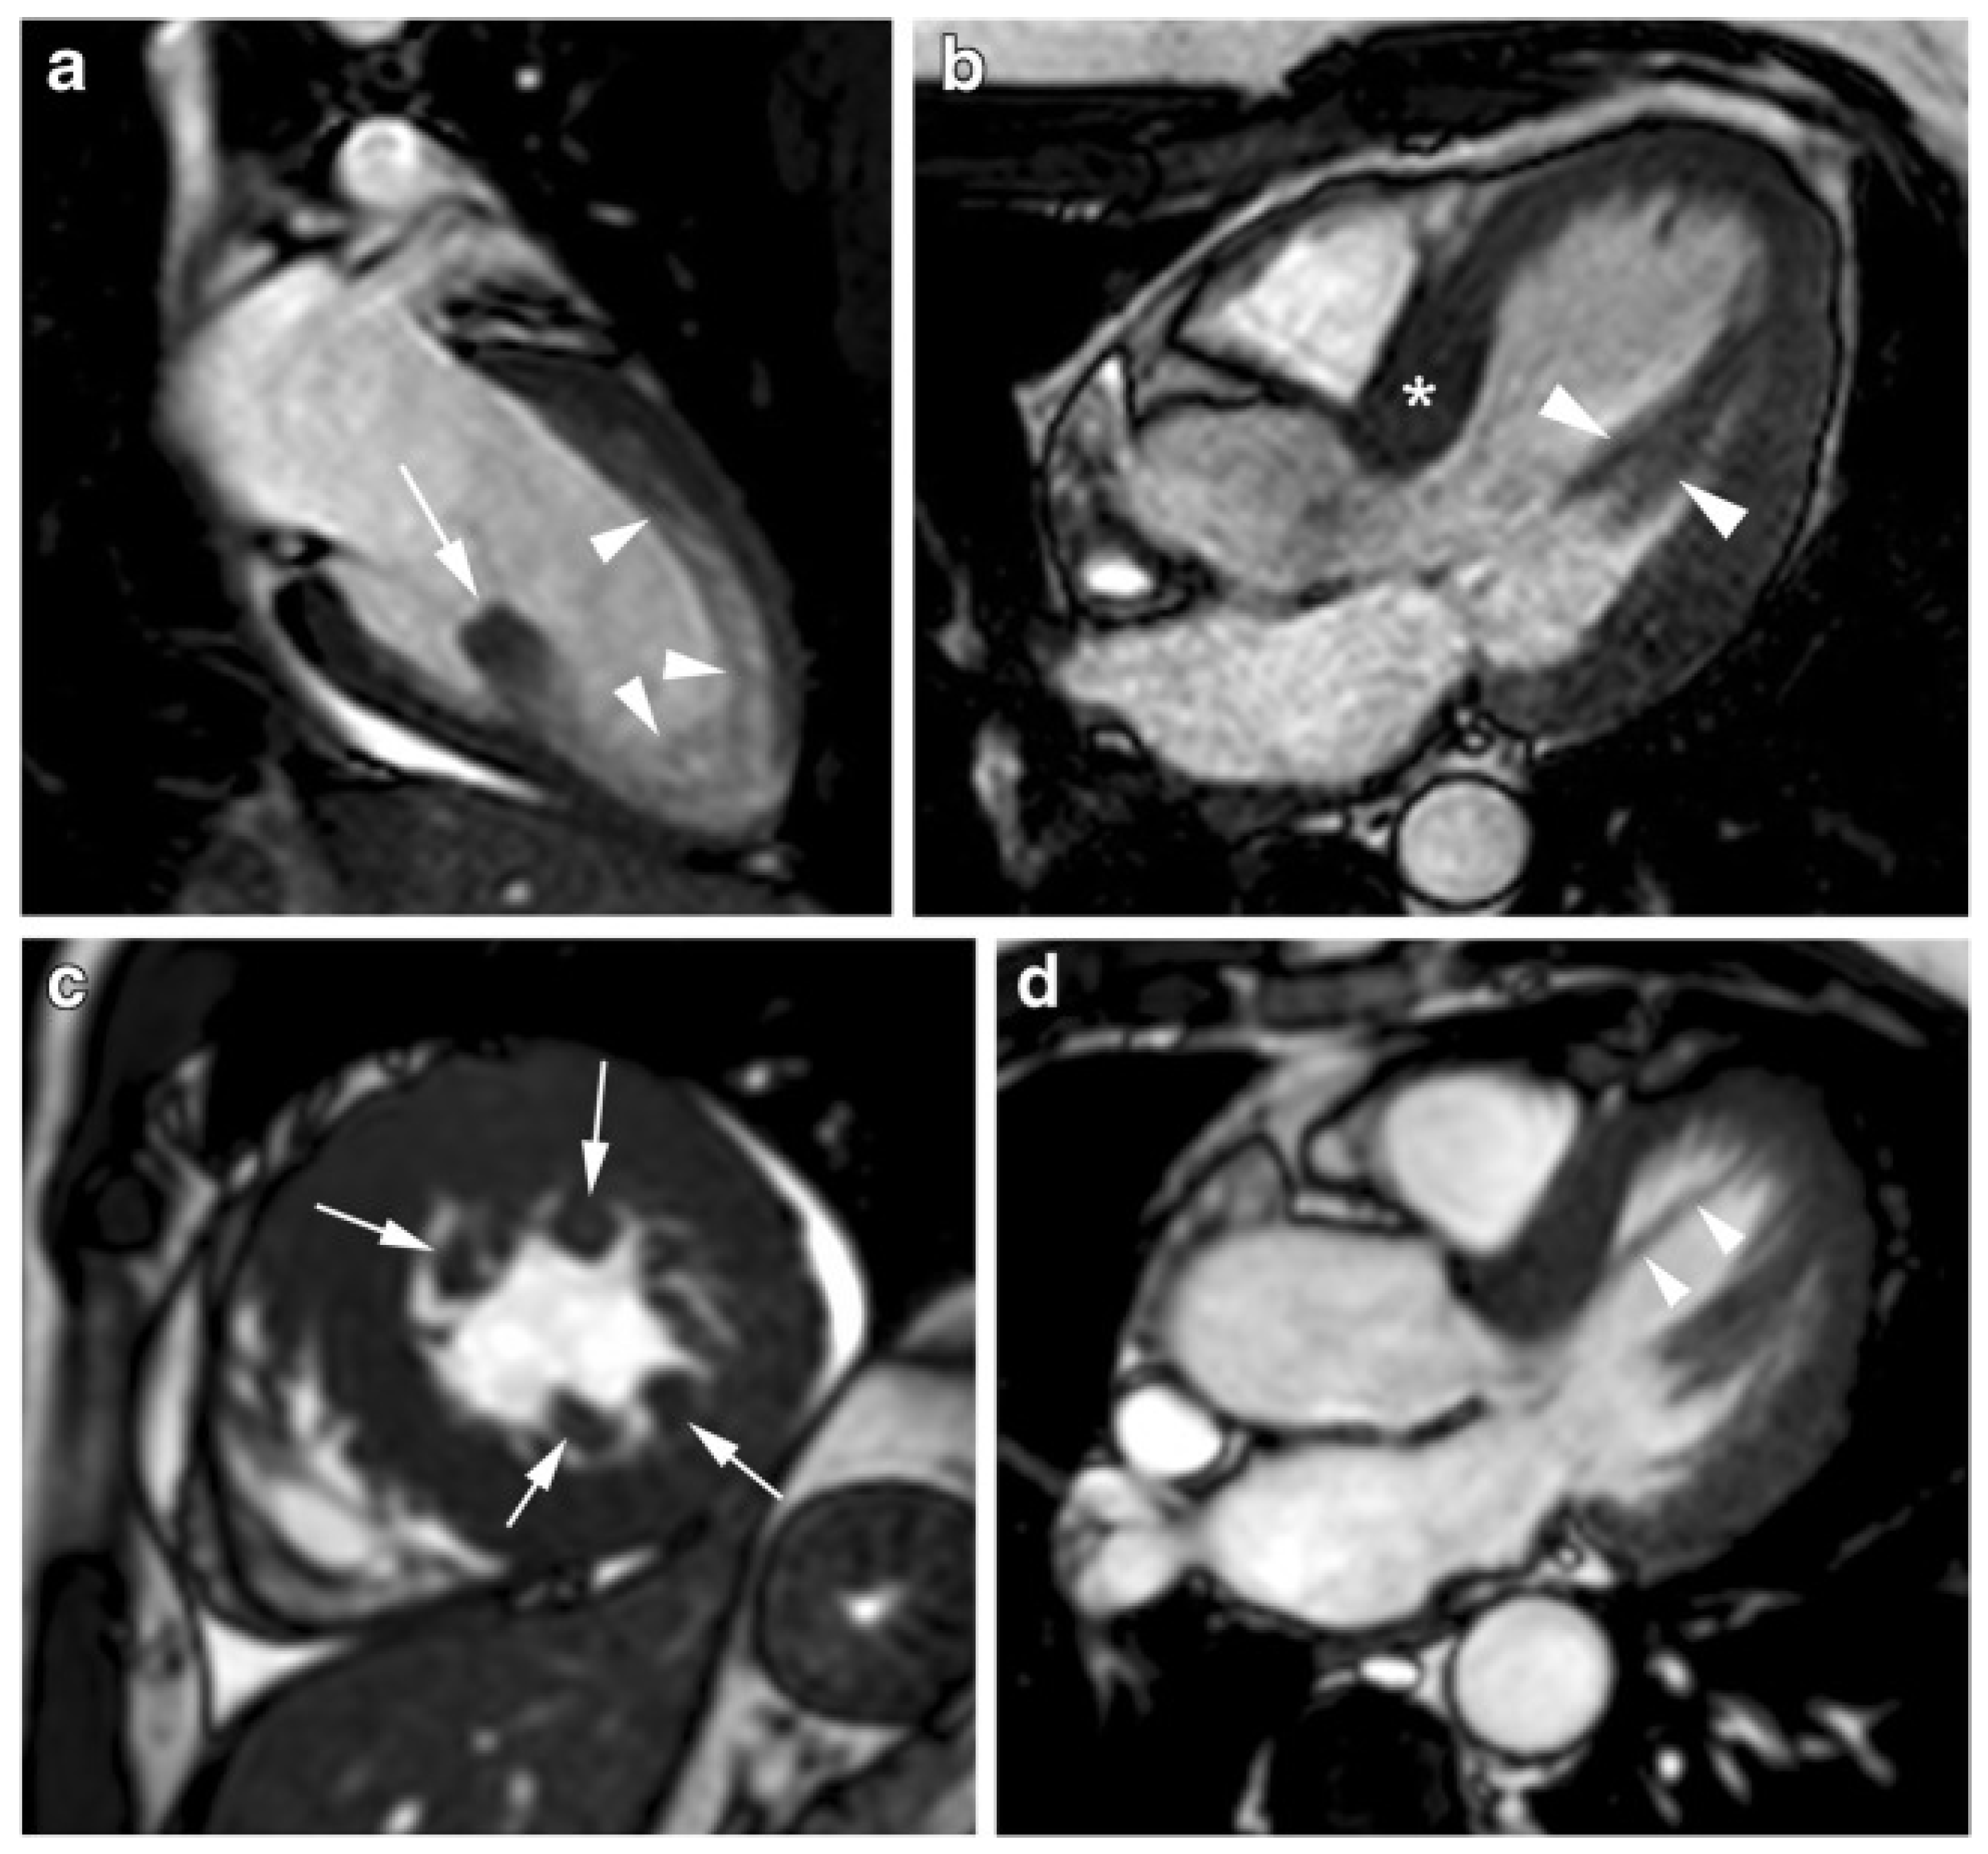

3.6. CMR Evaluation of Mitral Valve and Papillary Muscles

3.7. CMR Evaluation of Left Atrial Dimensions and Function

4.3. Differential Diagnosis with Infiltrative Cardiomyopathies